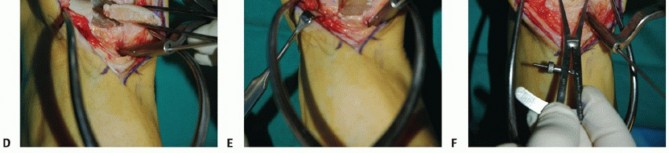

- TECH FIG 1 • A. Medial incision and anterior ankle arthrotomy. B. Opening of the posterior tibial tendon sheath. C. Predrilling of medial malleolus. Kirschner wire for trajectory of medial malleolar osteotomy has already been inserted and its position confirmed with fluoroscopy. D. Fluoroscopic image demonstrating Kirschner wire being used as a guide to direct the saw. E. The periosteum is scored perpendicular to the tibial shaft, at the level of the osteotomy. F. Medial malleolar osteotomy. Care must be taken to protect the posterior tibial tendon. (continued)

Predrill the medial malleolus across the proposed osteotomy site (TECH FIG 1C).

We routinely use two small fragment malleolar screws and predrill with the corresponding drill. Obtain fluoroscopic confirmation that the drill bits are in the proper trajectory.

Place a Kirschner wire obliquely to define the trajectory of the medial malleolar osteotomy (TECH FIG 1C).

Place it slightly proximal to the desired osteotomy so it can function as a guide but not interfere with the saw (TECH FIG 1D).

Confirm the optimal Kirschner wire trajectory with intraoperative fluoroscopy.

- TECH FIG 1 • (continued) G. Fluoroscopic image showing near-complete bone cut. H. Release of posterior tibial tendon sheath from distal medial malleolus to allow mobilization.

Determine a plane for the osteotomy in the anteroposterior (AP) plane that is perpendicular to the longitudinal axis of the tibia. We find it helpful to score the osteotomy in the periosteum from anterior to posterior to determine this level (TECH FIG 1E).

With a microsagittal saw oriented correctly in both planes, the osteotomy is initiated (TECH FIG 1F).

Obtain intraoperative fluoroscopy shortly after initiating the osteotomy; leave the saw blade in place to confirm proper trajectory. If incorrect, a subtle adjustment is still possible (TECH FIG 1G).

Continue the osteotomy with the saw to the subchondral bone and then complete the osteotomy with a chisel.

A fluoroscopic spot view allows the surgeon to confirm that the osteotomy is appropriate and is not violating the talar cartilage.